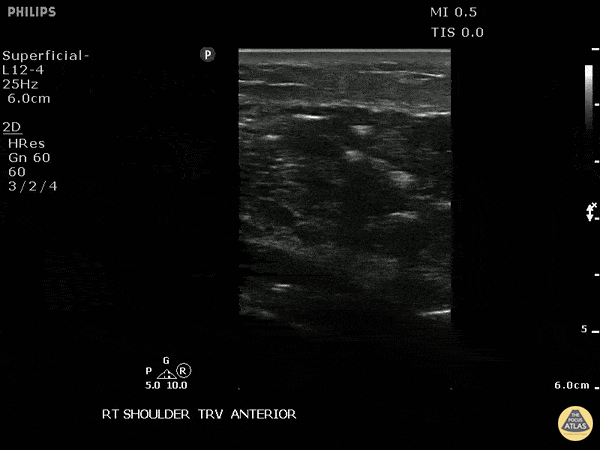

This is a transverse view of the anterior shoulder of a patient who presented to the emergency department with a fever and shoulder pain causing limited mobility. Looking closer, we can observe hyperechoic densities caused by air within the tissues, otherwise no signs of septic joint or bursitis. Image courtesy of Robert Jones DO, FACEP @RJonesSonoEM Director, Emergency Ultrasound; MetroHealth Medical Center; Professor, Case Western Reserve Medical School, Cleveland, OH View his original post here